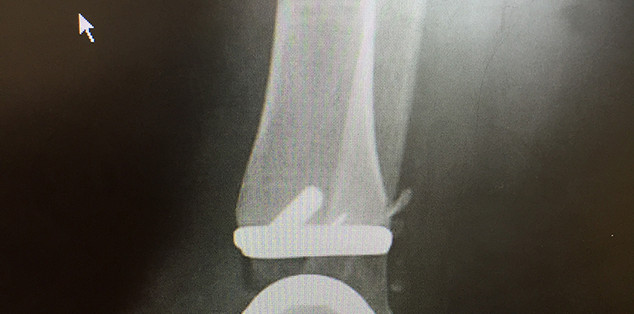

The experience for the foot and ankle fellow at the Rothman Orthopaedic Institute is second to none. As a Foot and Ankle division, we see approximately 40,000 patients and perform over 3,000 procedures annually. All areas of foot and ankle are covered and the benefit of our high volume can be seen with how comfortable our fellows become, even with rare and challenging surgical scenarios. As a division we perform over 160 total ankle replacements per year and are actively engaged in the design, development and improvement of these devices.